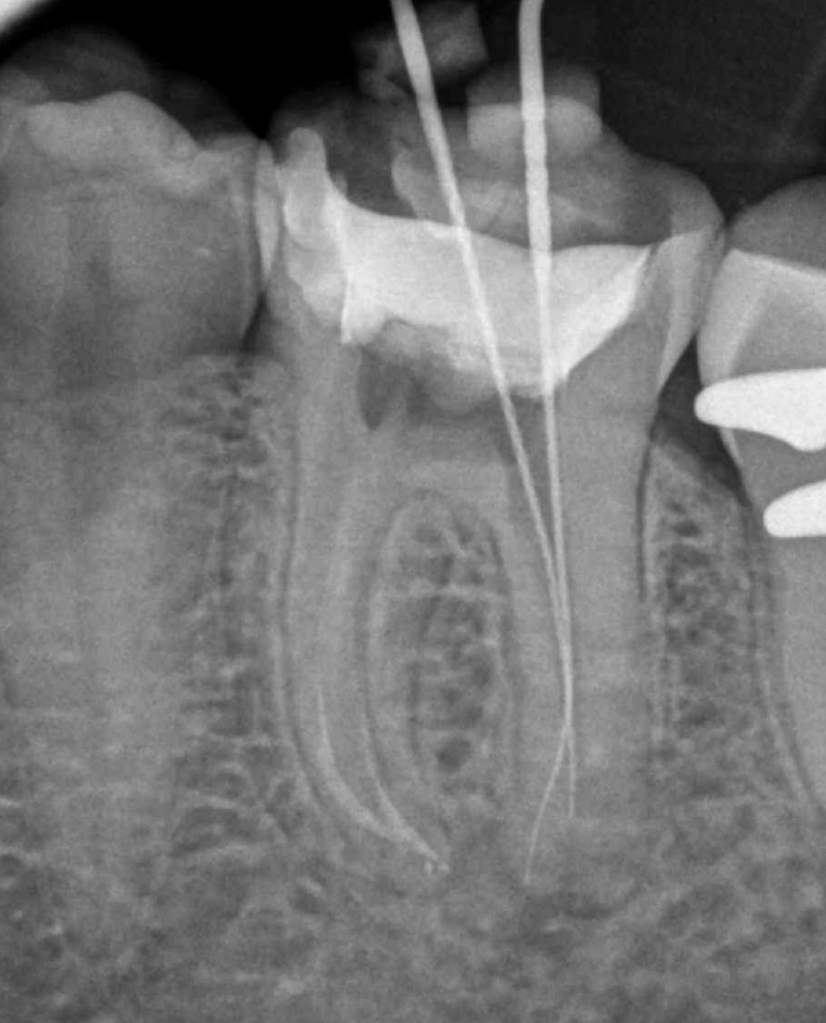

Molar inferior, conducto CM